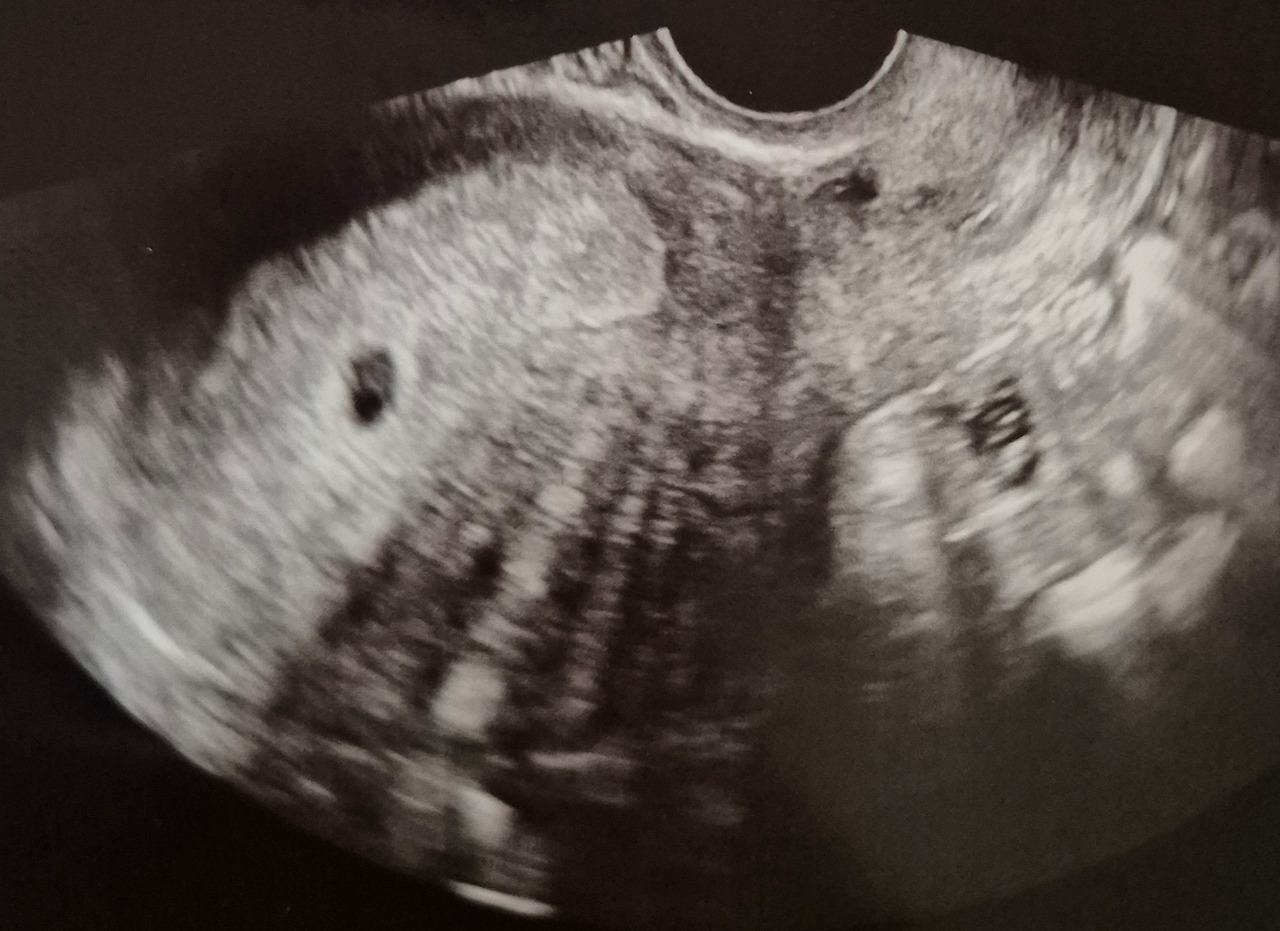

오늘은 초음파 검사하는 날..!

분명 전날 보건소에서는 아기집만 보이던 복복이집에...! 난황이!!!!

우리 복복이 대단해 ㅎㅎㅎ담주면 우리 아가 볼 수 있겠다ㅎㅎㅎ

오늘도 유산방지 엉덩이주사..(일명 돌주사로 불리는 바로 그 주사...!!)를맞고 유산방지약 7일 치 처방을 받았다 담주에 다시 방문하라시는거 보니 담주정도면 우리 복복이를 볼 수 있을 거 같다 ㅎㅎ